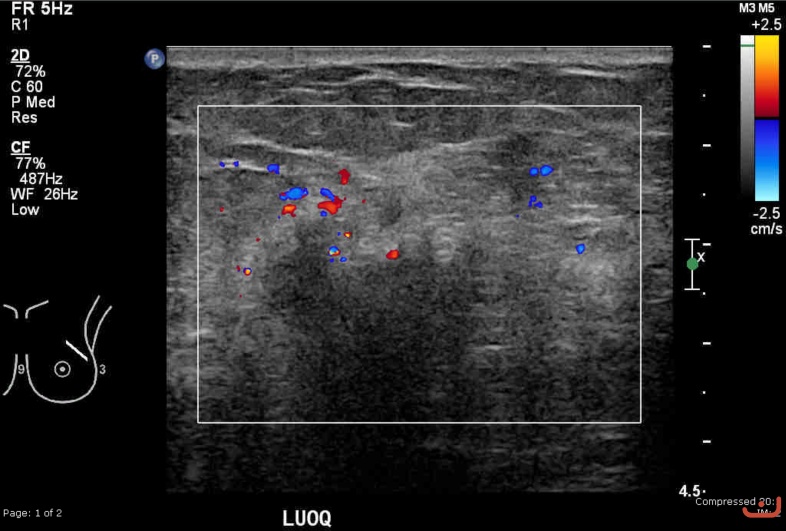

Malignant solid mass

Friday, 22 May 2015